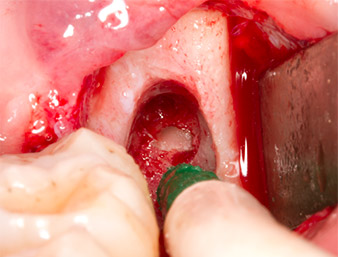

After block and local anaesthesia, the operating site was opened up and the soft tissue exposed for buccal retromolar access (Fig. 3).

The tissue above the root remnant was not completely ossified and consisted for the most part of granulation tissue modified by inflammation (Fig. 4).